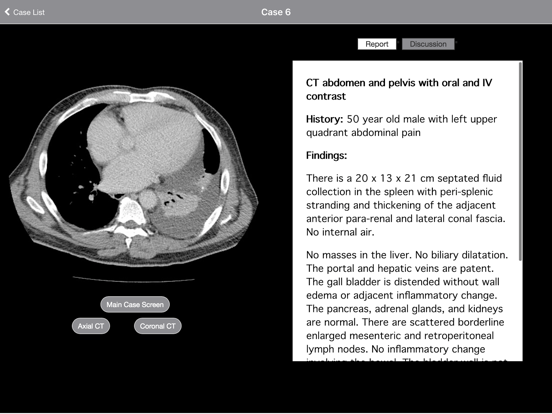

Each case is presented as a complete CT or MRI scan that you can scroll through as if at a PACS workstation. Multiple sequences in multiple planes are presented for every case. Report, short discussions, and pathology/clinical followup are presented for each case.

- Dr. Daniel Cornfeld is a consultant radiologist at Haoura Tairawhiti in Gisborne, New Zealand. Prior to that he was an Associate Professor of Diagnostic Radiology at Yale University School of Medicine. The narratives contain his opinions (based on the medical literature) and reflect the way he would teach if you were one of his students. The information in this app does NOT constitute medical advice and is meant to compliment and augment, not replace, pre- or co-existing medical education. Neither Haoura Tairawhiti nor Yale University School of Medicine have officially endorsed this content.